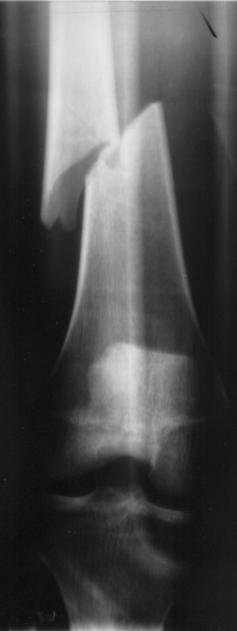

I’ve worked in many medical settings, and have seen lots of illnesses and injuries over 30+ years of doctoring.  Despite all that experience, I really don’t do well with badly broken bones.  Basic wrists and fingers and ankles are no problem but open compound and comminuted fractures (i.e. “crushed bones”) are downright terrifying.  It appears to me they can never be pieced back together.   Even looking at the xrays makes me cringe.  I avoided doing a surgical orthopedic rotation during my training because I knew I’d have issues with the saws and the smells involved in fixing bad fractures.  And witnessing the pain is unforgettable.